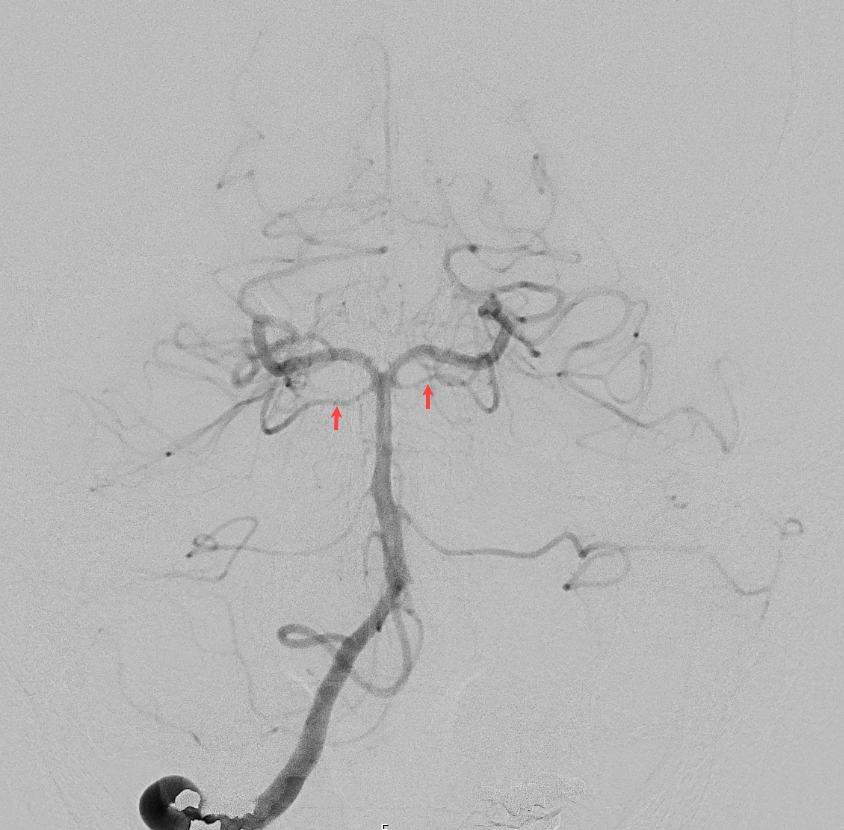

Abbildung

Bildgebung

Der Goldstandard zur optimalen Darstellung der Arteria cerebelli superior ist die digitale Subtraktionsangiographie.